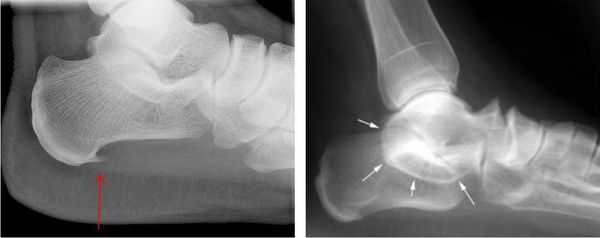

Для выявления полных и частичных разрывов ахиллова сухожилия применяют рентгенографическое исследование (по принципу маммографии). Последняя также эффективна для дифференциации разрыва из-за тендонита. Точность ее в одном наблюдении достигала приблизительно 75%. Следовательно, если врач центра неотложной помощи затрудняется разделить эти два повреждения, следует иметь в виду, что вышеупомянутое рентгенографическое исследование поможет поставить верный диагноз.

При подозрении травматической природы синдрома проводится рентгенография голеностопного сустава и стопы. Во время исследования также можно обнаружить костные выступы и остеофиты.